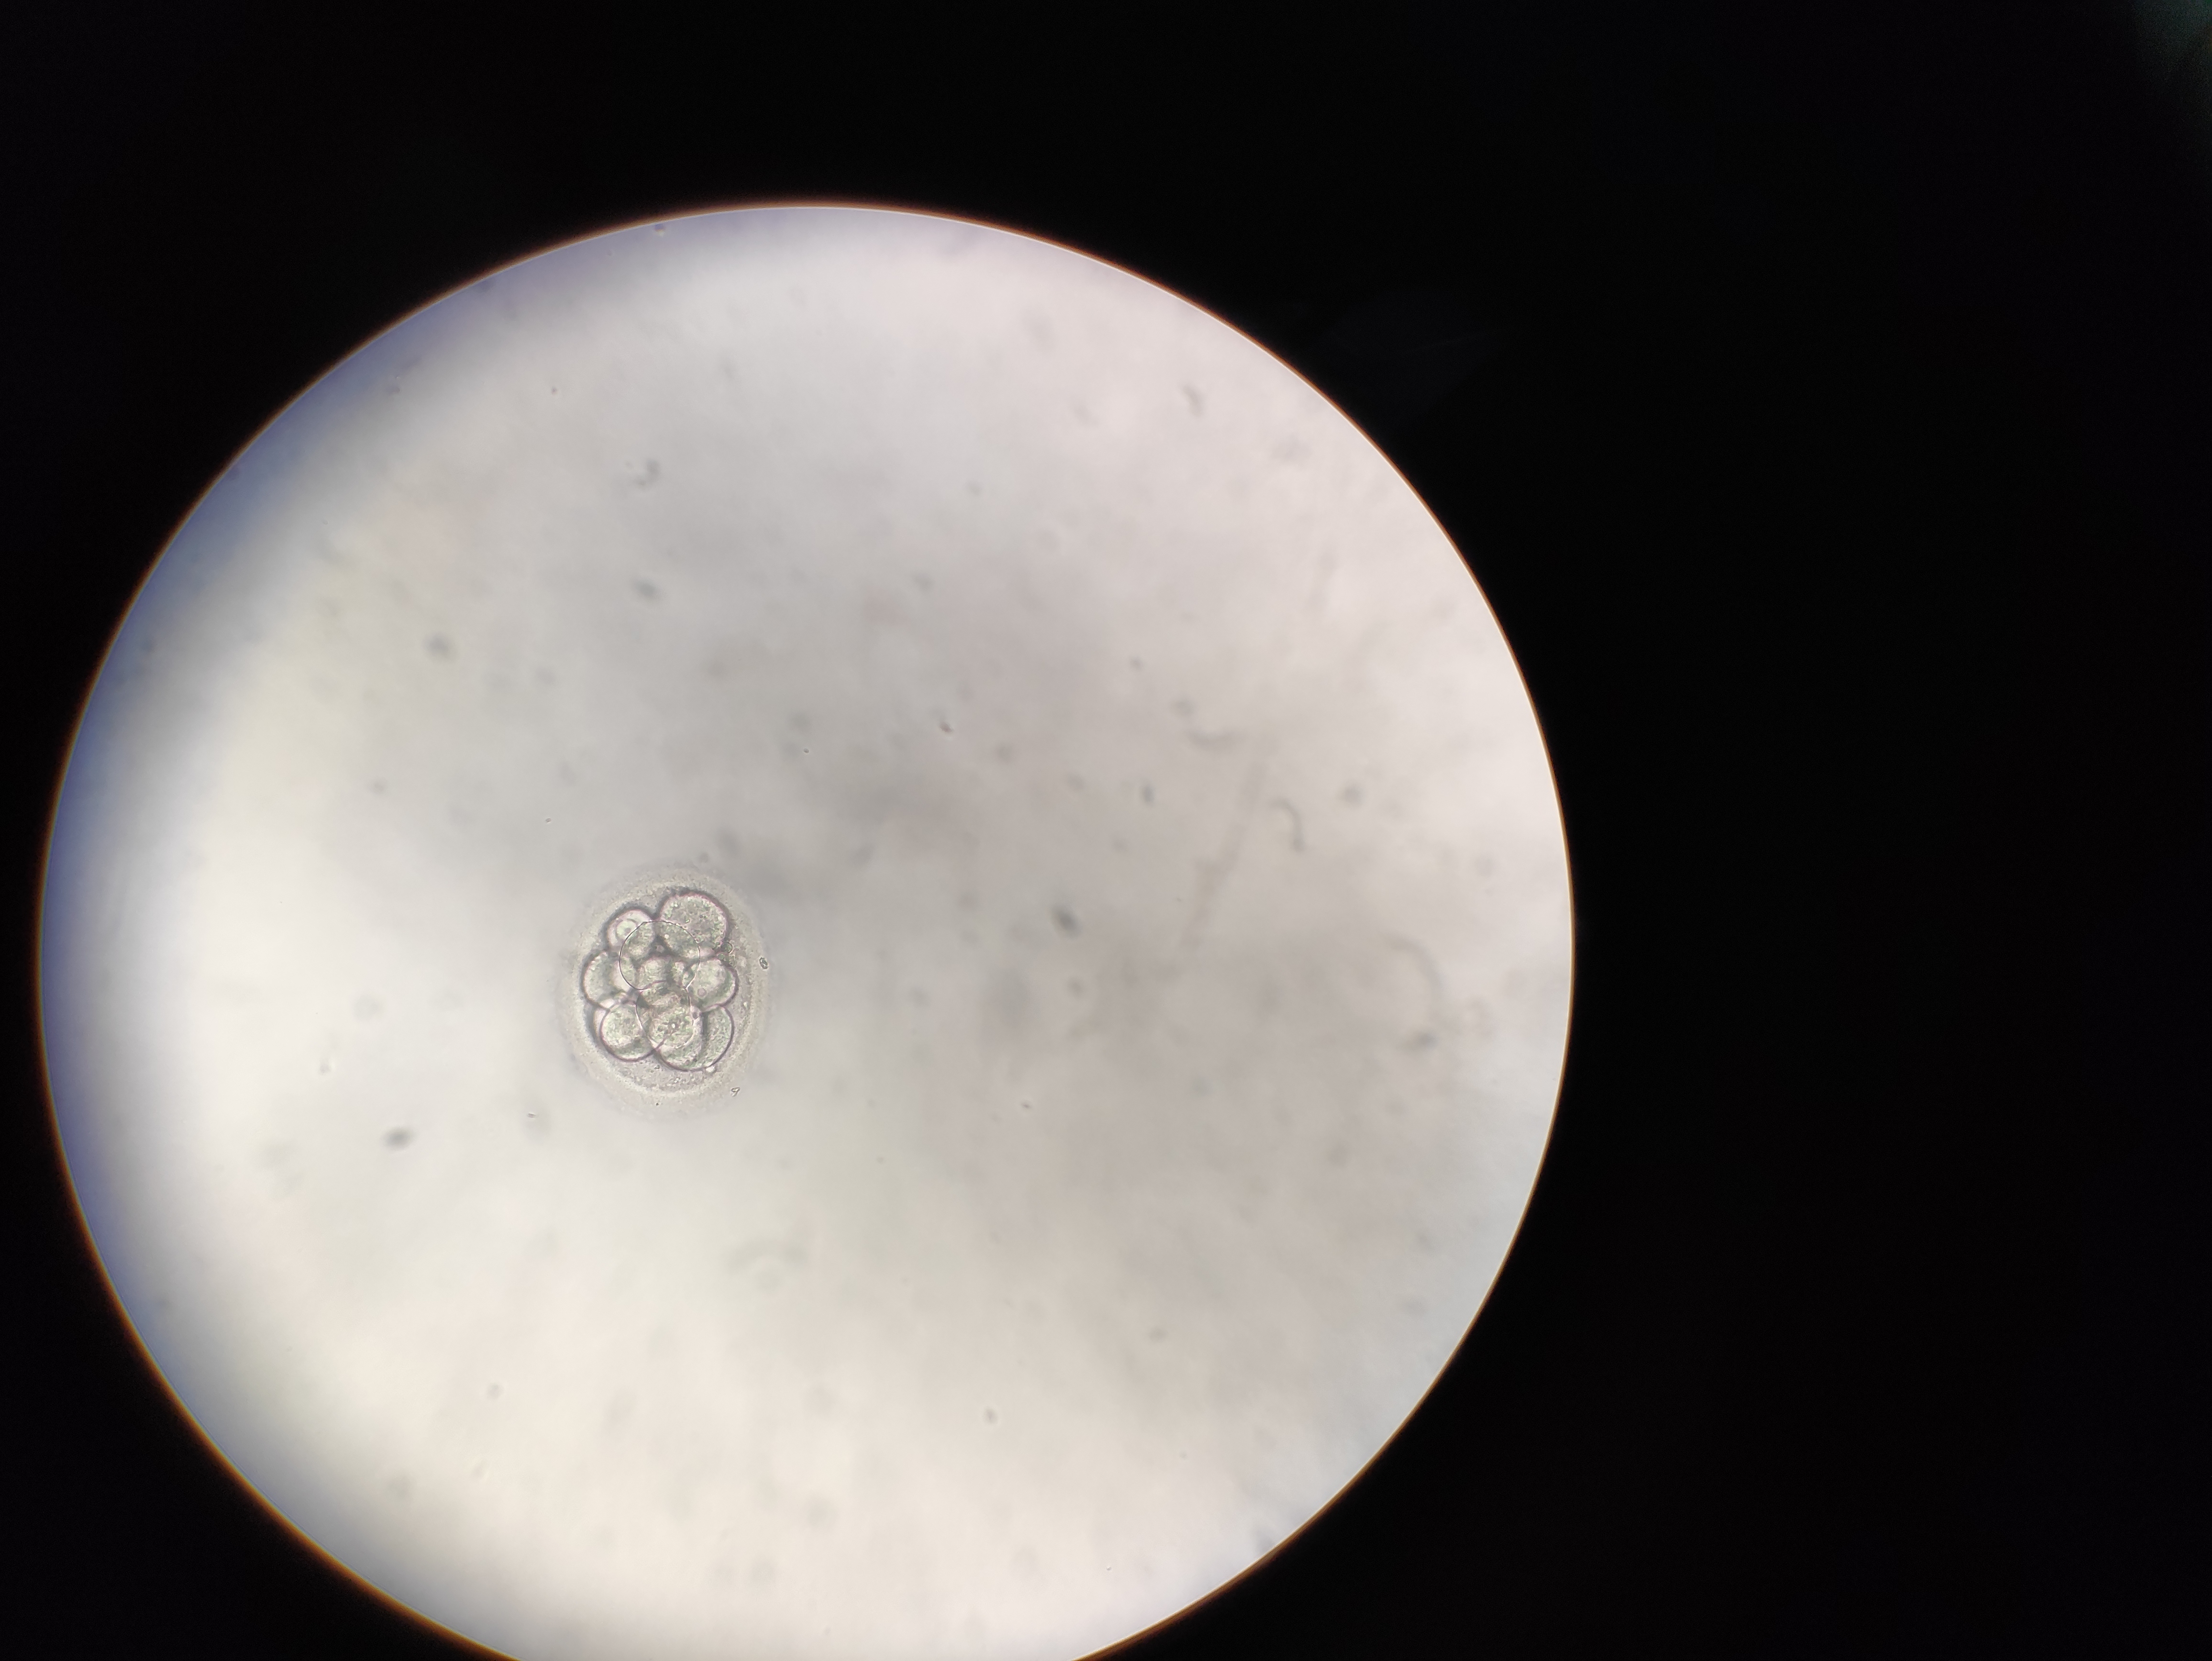

Hallo zusammen,

Embryo Bewertung